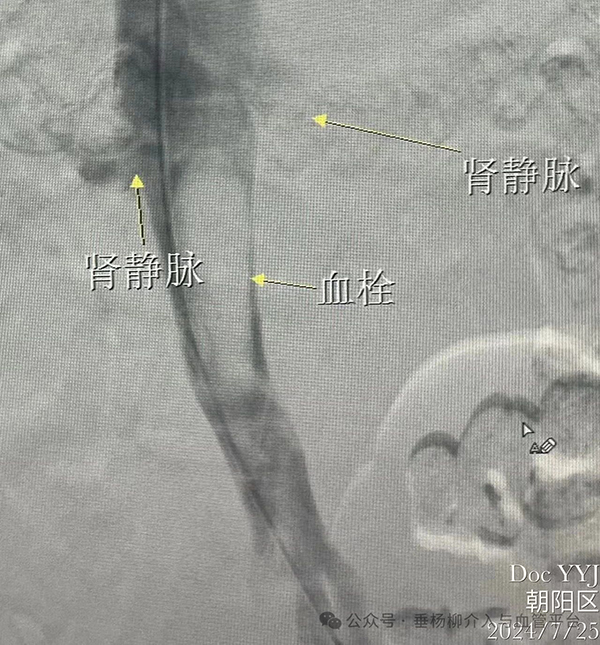

下肢静脉血栓是指血液在下肢静脉内不正常地凝结,阻塞管腔,导致静脉回流障碍的一种疾病。常见原因包括静脉壁损伤、血流缓慢和血液高凝状态。患者常表现为下肢肿胀、疼痛、皮肤温度升高及浅静脉扩张等症状,严重时可导致肺栓塞,危及生命。针对下肢静脉血栓的治疗,根据病情严重程度,可能包括药物治疗、物理治疗、手术治疗(如下腔静脉滤器植入结合溶栓治疗)或介入治疗(如导管溶栓、机械血栓清除等)。